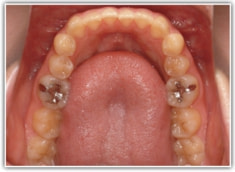

治療後(1年8ヶ月後)

検査時レントゲンパントモ

現代人には珍しく8番(親知らず)が直立して萌出しています。